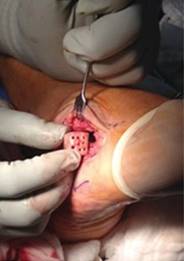

Se realizó la biopsia transquirúrgica, la cual reveló abundante tejido fibroconectivo con osteoblastos y nidos de hueso trabecular con matriz ósea y tejido osteoide e hipervascularidad del estroma, aumento de la celularidad sin atipias y escasas células gigantes multinucleadas (Figura 4); se clasificó como Enneking 2. Se inició tratamiento con resección y curetaje del tumor, crioterapia y colocación de injerto tricortical en el defecto en cuboides (Figura 5).

Figura 4: Resultado histopatológico microscópico.

Figura 5: Colocación de injerto óseo tricortical.